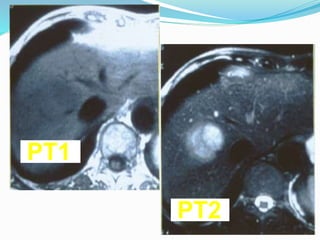

Resonancia Magnética

Secuencias rápidas,estudios hemodinámicos, adquisición

multifásica, Angio-RM

Contrastes:

•Gadolinio, Ferrumóxidos, Ferritina (c.Kupffer)

•Manganesio, DPDP, Telescan (hepatocitos)

Sens.

> 3 cm 100 %

> 1 cm 52 %

< 1 cm 4 %

Global 55-93 %

T1 hipointensa

T2 hiperintensa

PT1

PT2

Resonancia Magnética Secuencias rápidas,estudioshemodinámicos, adquisición multifásica, Angio-RM Contrastes: •Gadolinio, Ferrumóxidos, Ferritina (c.Kupffer) •Manganesio, DPDP, Telescan (hepatocitos) Sens. > 3 cm 100 % > 1 cm 52 % < 1 cm 4 % Global 55-93 % T1 hipointensa T2 hiperintensa